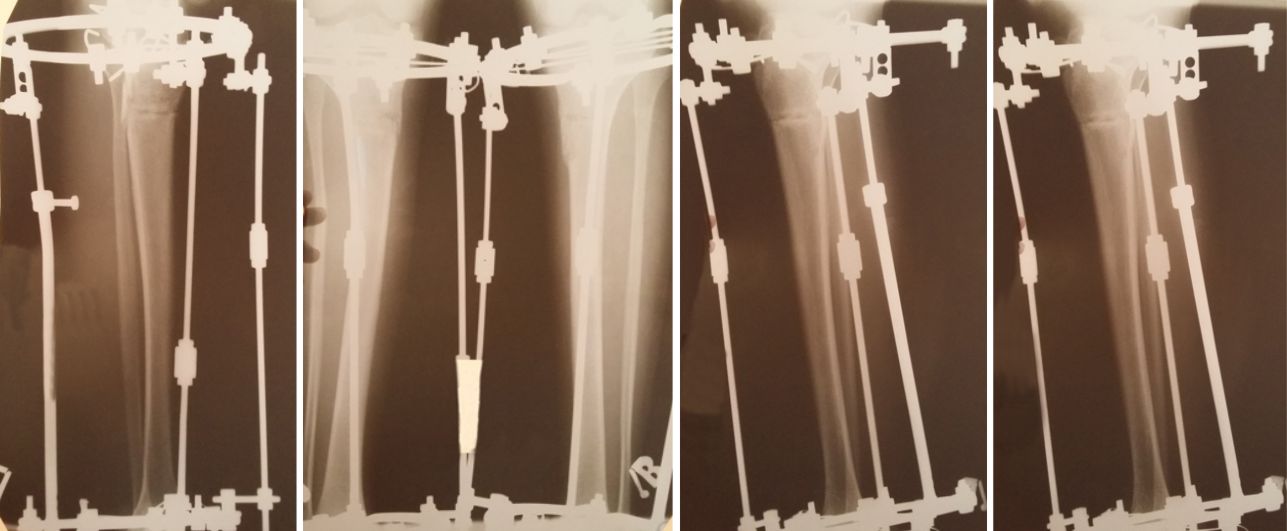

Рентген в 60 дней с момента операции

Сращение отличное! В 85 дней планируем снятие аппаратов!!!

Дата операции 29.04.2017г.

Дата снятия аппаратов 25.07.2017г.

Срок лечения 85 дней.